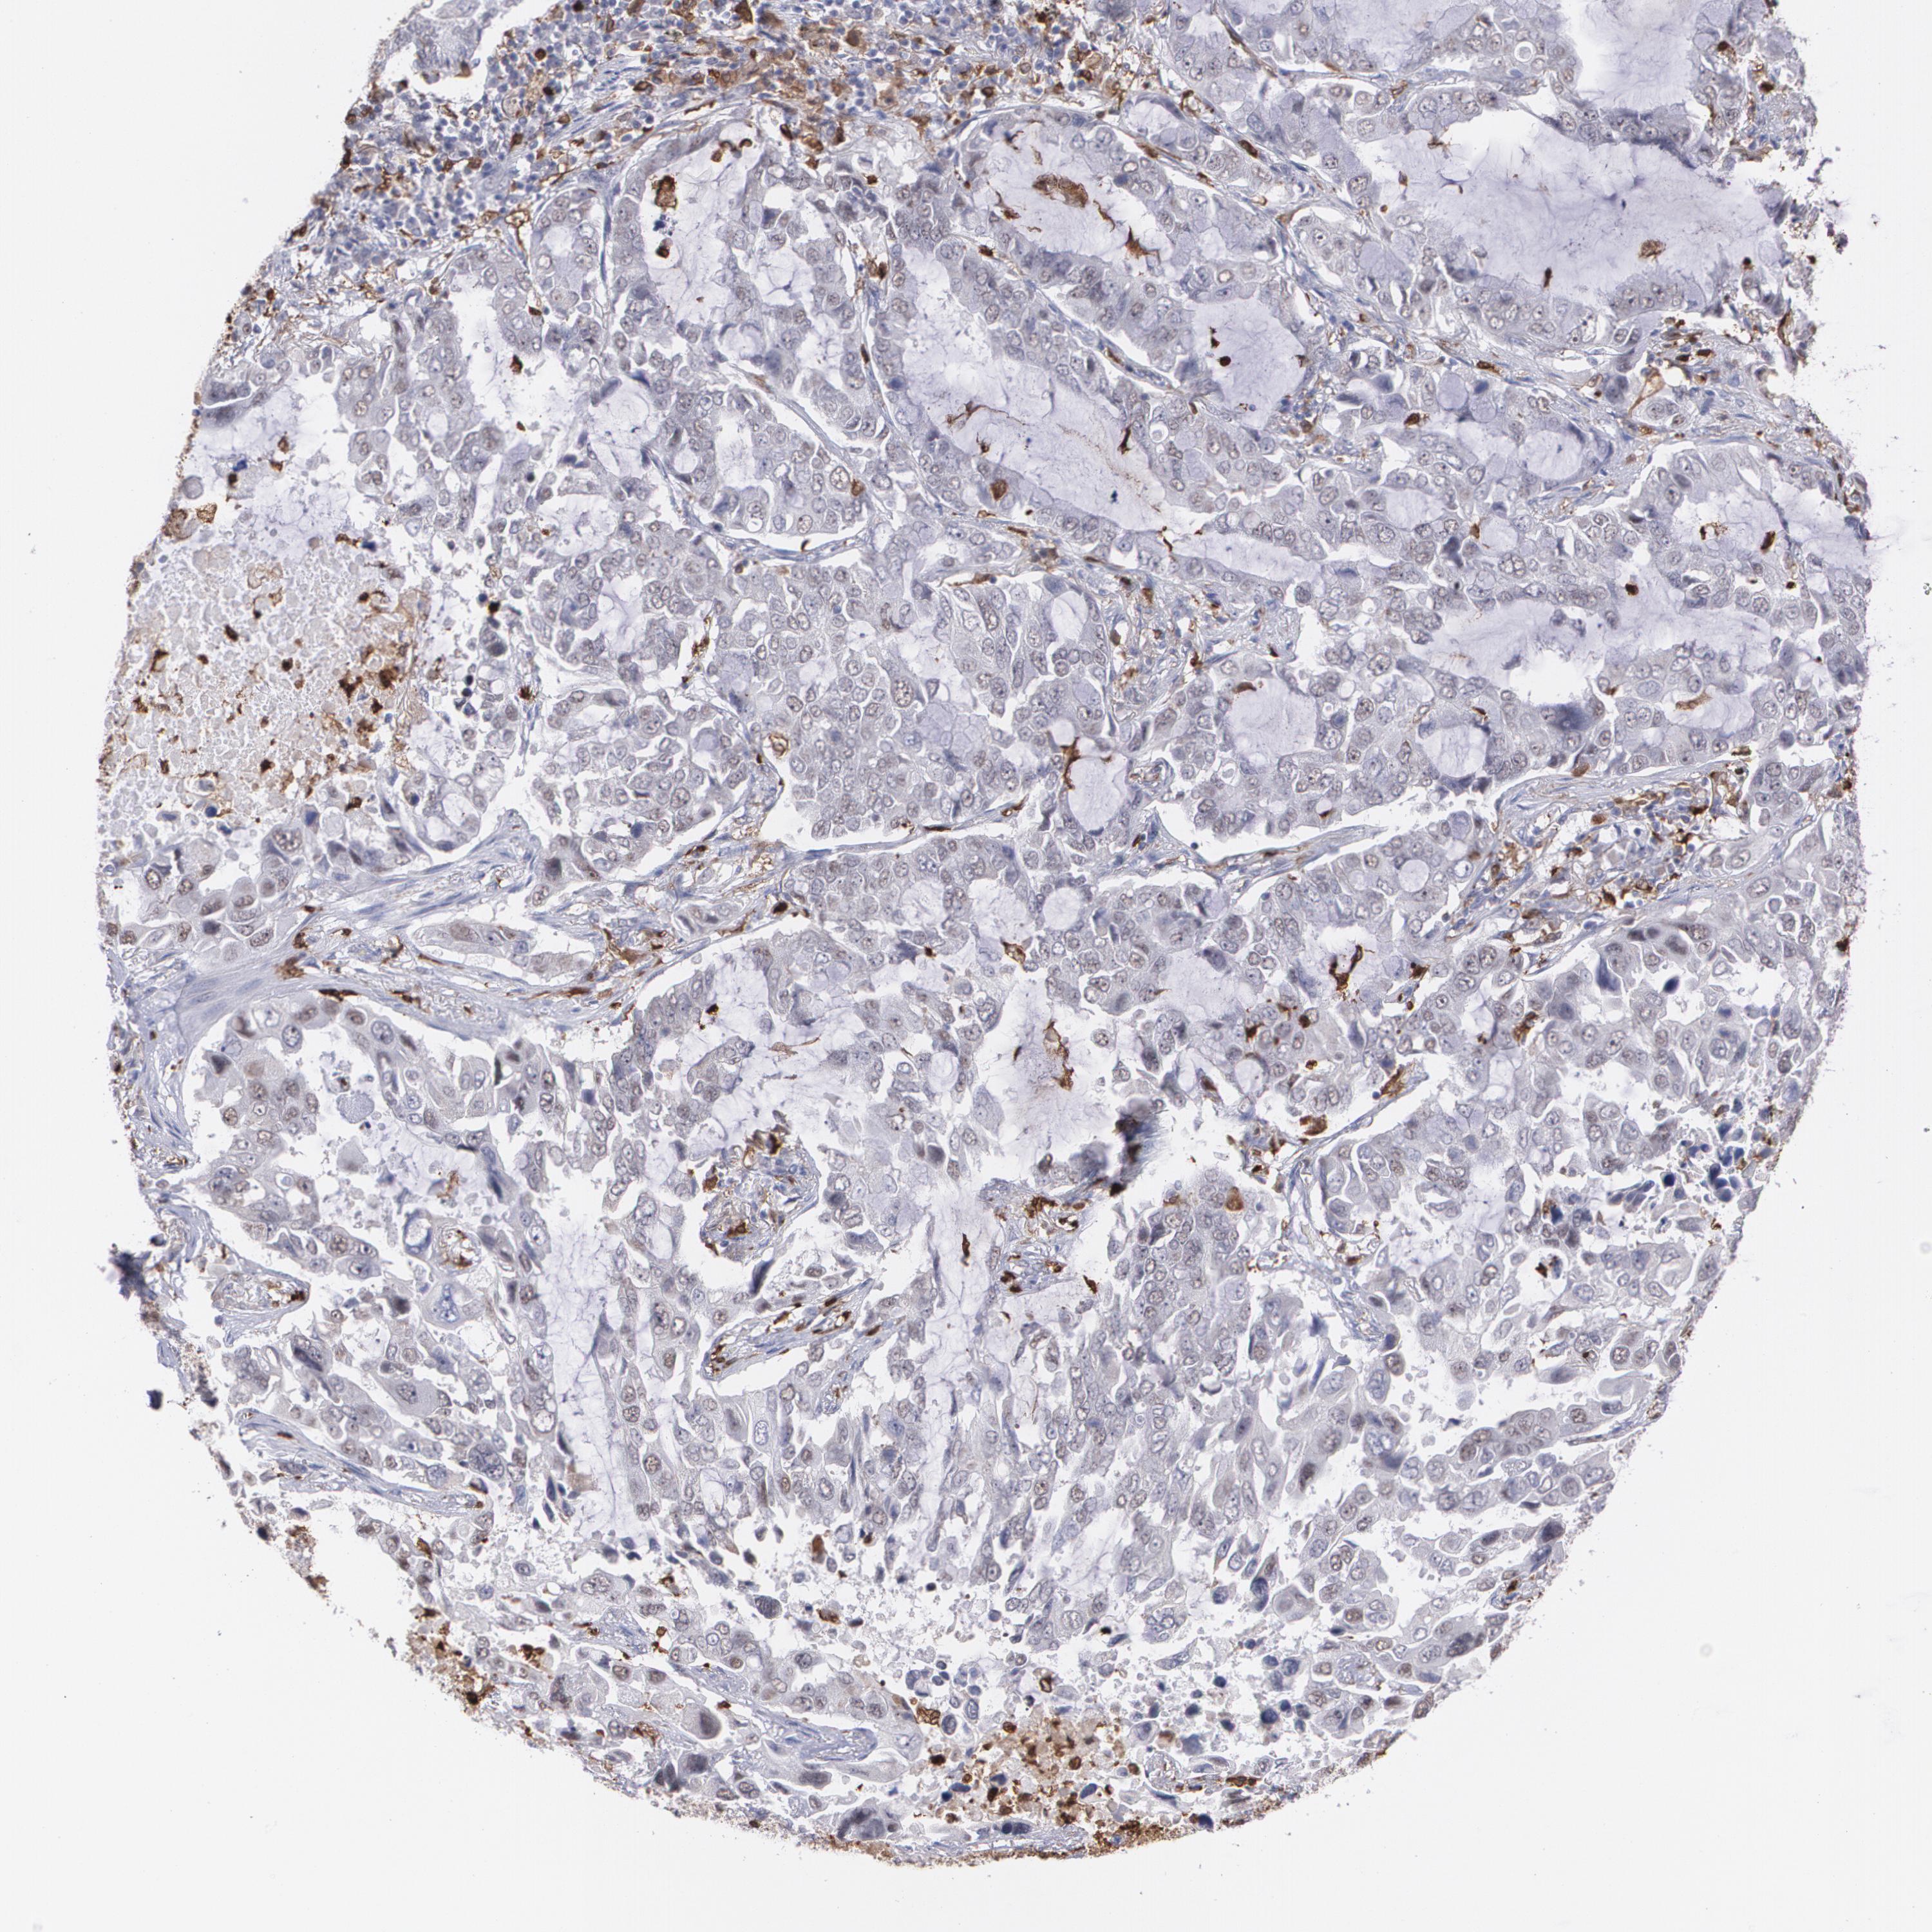

CANCER LUNG CANCER Show tissue menu

LUAD TCGA LUAD VALIDATION LUSC TCGA LUSC VALIDATION PROTEIN LUAD CPTAC PROTEIN LUSC CPTAC PROTEIN EXPRESSION